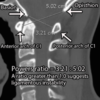

Power’s Ratio

Basion to posterior arch/Opisthion to anterior arch

Normal is 1

Abnormal: occipito-atlantal instability